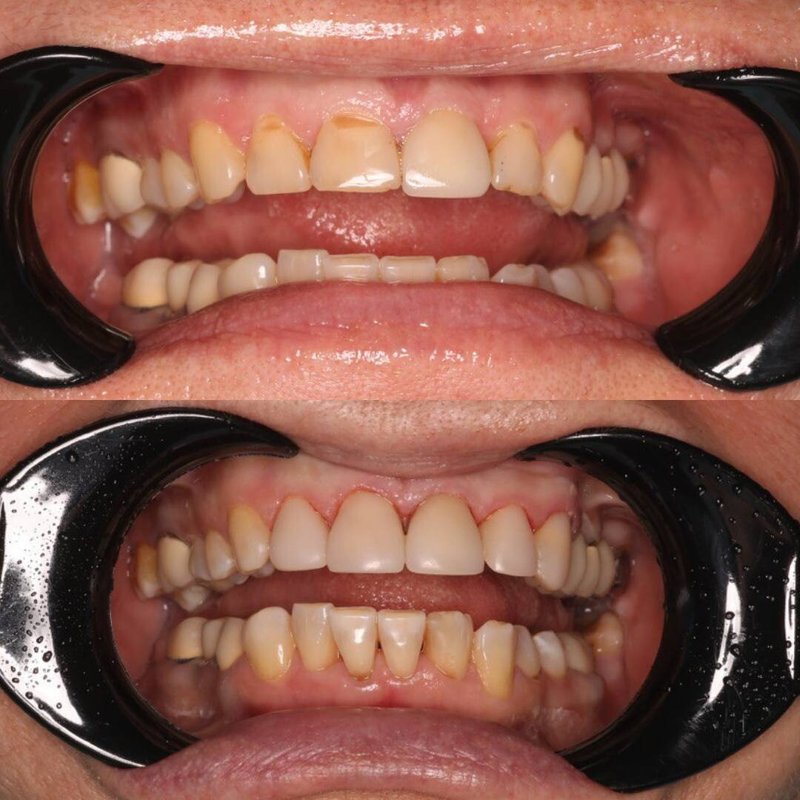

Фотогалерея

Если вы собираетесь добиться сияющей улыбки, то работу над ней лучше доверить экспертам. В стоматологической клинике Династия Н имеется специализированное оборудование для того, чтобы ваши зубы снова стали белоснежными. В нашей стоматологии оказывают услуги лечения кариеса, удаления зубов, компьютерной томографии, отбеливания, исправления прикуса, рентгенологической диагностики, изготовления имплантов, а также установки металлокерамики, брекетов, имплантов, виниров. С нами ваша улыбка будет яркой, а зубы крепкими!